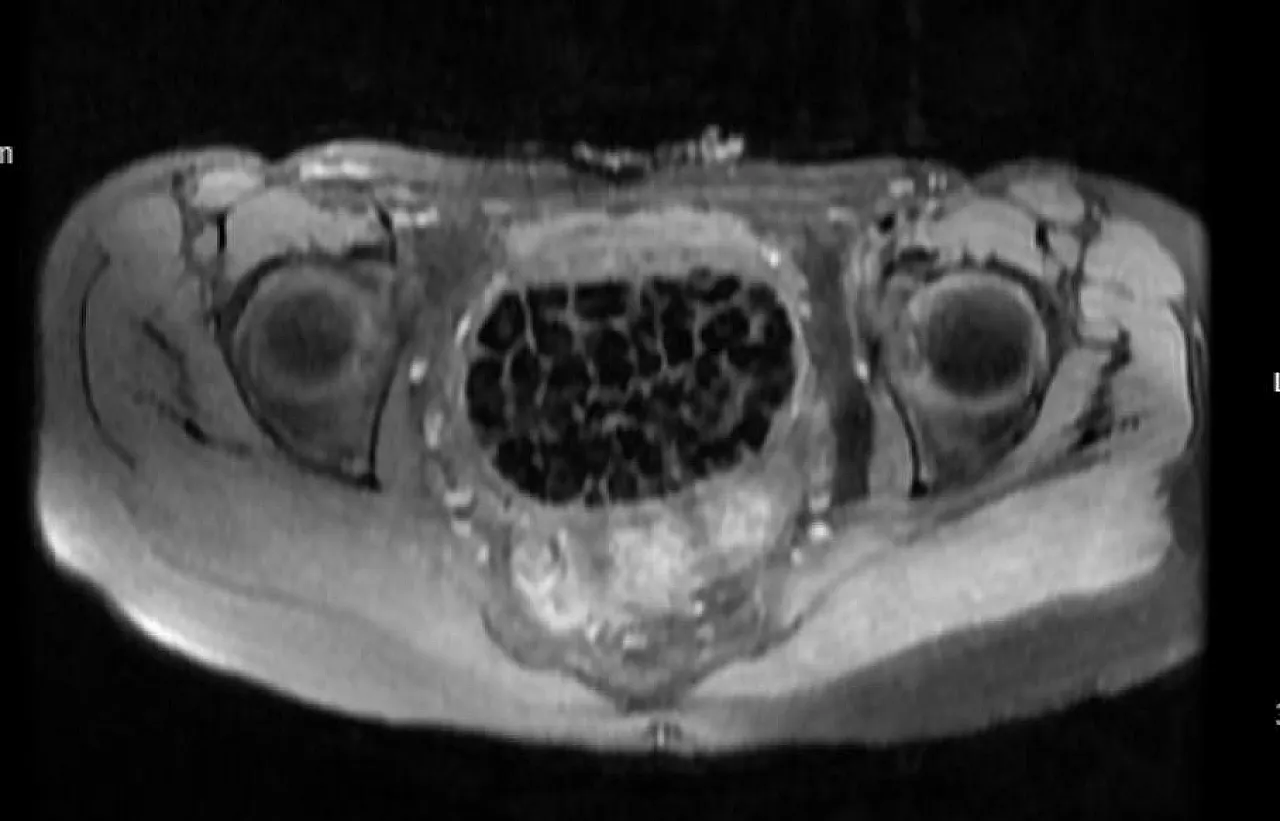

Ameliyatı gerçekleştiren Üroloji Uzmanı Doç. Dr. Erkan Erkan, hastanın geçmişte art arda ameliyatlar geçirdiğini ve yapılan görüntülemelerde mesane arkasında taşlarla dolu bir kese tespit ettiklerini belirtti. Ek görüntülemelerle taşların vajinal boşlukta oluştuğu kanaatine varıldığını ifade eden Erkan, operasyon sırasında toplam 287 taşın çıkarıldığını ve bunun literatürde son derece nadir görülen bir durum olduğunu vurguladı.

Jinekolojik Onkoloji Uzmanı Op. Dr. Emin Erhan Dönmez ise hastanın uzun süredir karın ağrısı şikayetiyle geldiğini, yapılan muayenede vajen bölgesinde göllenen idrar nedeniyle taş oluştuğunun tespit edildiğini aktardı. Dönmez, mesaneden vajene geçiş sırasında tüm vajenin taşlarla dolu olduğunu gördüklerini ve en büyüğü 2,5 cm olan 287 taşın çıkarıldığını belirtti. Bu kadar yüksek sayıda taşla karşılaşmanın kendileri için de şaşırtıcı olduğunu ifade eden Dönmez, vakayı literatürde benzeri olmayan bir örnek olarak değerlendirdi.